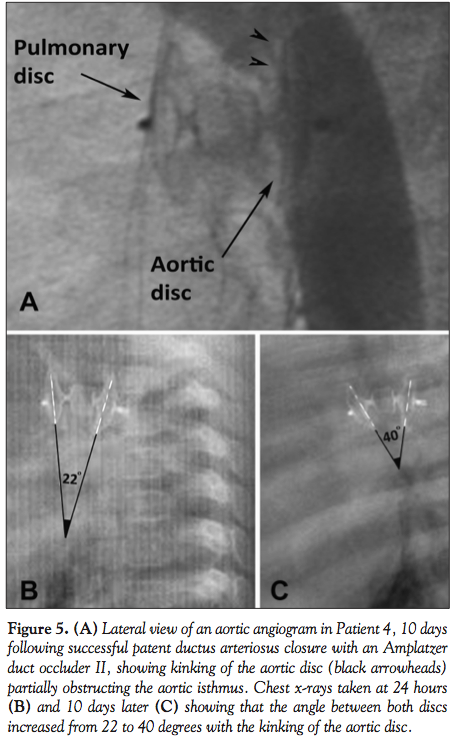

For the ADO II, immediate closure was achieved in 73.8% of the cases (31/42 patients), rising to 95.2% (40/42 patients) at 24 hours, but decreasing again at 10 days to 92.8% (39/42) and remaining like that at 6 months. The ADO II device that failed secondarily at 10 days was in a 5-month-old, 6.6 kg baby girl, with a 3 mm type A PDA (Patient 4 in Table 2 and Figure 2). It was successfully closed with a 6-6 device with no residual shunt or aortic obstruction. However, the 10-day follow-up showed a residual shunt with severe aortic obstruction due

to a secondary kinking of the aortic retention disc (Figure 5). The device was surgically retrieved and the PDA ligated. There were also 2 recovered failures in the ADO II group (Patients 5 and 6 in Table 2 and Figure 2); a 2.5-year-old, 10 kg girl with a 4.6 mm type A PDA, and a 3-year-old, 23 kg boy with a 4.8 mm type A PDA. Both were initially closed with 6-6 ADO II, and both devices migrated to the left pulmonary artery, a few minutes following their detachment. The devices were immediately retrieved percutaneously in both patients. In the first patient, the duct was closed with a 12-10 ADO I during the same procedure. In the second patient, the duct was closed with a 10-8 ADO I 6 months later.

Since its introduction in our practice, the ADO II proved to be a useful additional tool for PDA closure. It should be noted, however, that the ADO II is not yet available in the United States, and that phase 2 multicenter trials have just been completed. Complete definitive PDA closure was more rapidly achieved with the ADO II in our series — immediate closure in 74% of the patients, versus 40% with the ADO I. However, this finding proved to be irrelevant, since both devices were equally successful at 24 hours (95%). The ADO II has a 72 or 144 inner wire mesh, and most importantly, a 144 outer wire mesh, which promotes better occlusion, despite the lack of fabric that decreases the profile of the device. It is the device of choice for type C PDAs and ducts smaller than 5.5 mm.10 It shows a superior stability after deployment due to its symmetrical design.10 Nevertheless, the rate of migration in our series, as well as in the literature, was higher compared to ADO I.3,7,11 All of our failures with the ADO II have occurred in large, type A ducts with ampullas, in particular when the size is chosen to fit the minimal pulmonary diameter rather than the aortic ampulla. These ADO II failures may be also related to both its physical features, such as flexibility and malleability, and the morphology of the ducts. In our opinion, one of the big advantages of the ADO II, flexibility, accounted for its failure in Patient 4. Flexibility, due to the presence of 2 articulations, became a disadvantage in this relatively young 6.6 kg baby. The aortic disc was not well applied to the aortic wall, and was continuously hit with the high-pressure stream of the aortic isthmic blood flow; this resulted in the secondary kinking and elongation of the device, with a hemodynamically significant aortic obstruction.

Other theoretical advantages of the ADO II may be incriminated in failures and act like double-edged swords. The symmetrical design of the device makes the arterial delivery more rapid and tempting, despite less control on the aortic disc. The multiple available sizes make it difficult to choose the correct size. A shorter device may lead to disc elongation and a loss in central disc diameter, thus causing a residual leak, or even dislodgment and migration. On the other hand, a longer device may lead to disc protrusion in either the aorta or pulmonary artery. Finally, malleability of the device may be linked to a higher rate of migration.12 In Patient 5 (10 kg, 4.6-mm wide, 11.5-mm long, type A PDA), we probably underestimated the duct diameter and didn’t take into account the cyclic variations (systole and diastole) which are significant in large ducts: a 30% variation for a 4.6 mm duct results in a diameter >5.5 mm, reaching the device’s superior limit. The ADO II migrated to the left pulmonary artery and was immediately retrieved. The duct was secondarily closed with an ADO I. In large, non-tubular ducts, and in short ones with a large aortic ampulla and fast tapering, the ADO I should probably be the first choice. The second ADO II migration occurred in a 23 kg patient with a very unusually shaped 19-mm long PDA (Figure 2; Patient 6); it had a large pulmonary ampulla, an uncommon tubular part, a 4.8 mm restriction, and then an aortic ampulla. The pulmonary ampulla was considered to be an aneurysm of the pulmonary artery and was excluded from the duct; hence, the rest of this duct could be classified as a classical type A PDA with fast tapering. With this strategic approach, the virtual reconstruction with a 6-6 ADO II seemed appropriate. Once again, the ADO II migrated to the left pulmonary artery a few minutes following its release. In this case, too, it was retrieved and the PDA was closed with an ADO I.